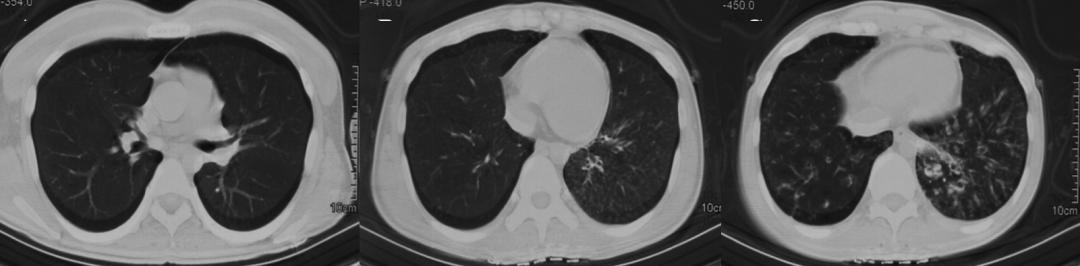

该患者雾化排痰及服用阿奇霉素2个月后复查,咳痰症状明显好转,咳痰次数和痰量减少,肺内病灶明显变淡变少(图6)。

图6.2022年1月胸部CT